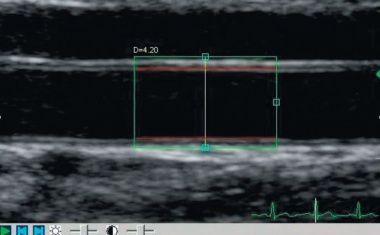

25.02.2011 - Jeder zweite Todesfall in Europa geht auf das Konto der Herz- und Gefäßkrankheiten. Das liegt mit daran, dass die Chancen der Herz- und Gefäßprotektion noch längst nicht...